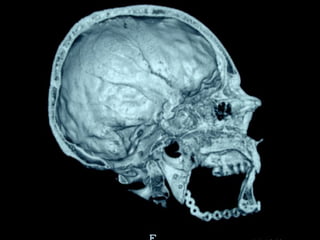

Trismus importante debido a que

El tumor ya rompió el hueso com-

Pacto de la cara interna de la

Mandíbula y empezó a tomar el

Músculo pterigoideo interno y

Sierra de GigliSierra de Gigli

Luxación de hemimandíbula

Pieza quirúrgica

Plantilla flexible para dar forma previa al implante

Se respetó el cóndilo para anclar la prótesisSe respetó el cóndilo para anclar la prótesis

Límite tumoralLímite tumoral

Area de lisis ósea a nivel de la línea

Miliodes que contracturó los músculos

Milohioideo y pterigoideo interno

Dificultando la deglución y determinando

Trismus importante.

48 horas de post-operatorio